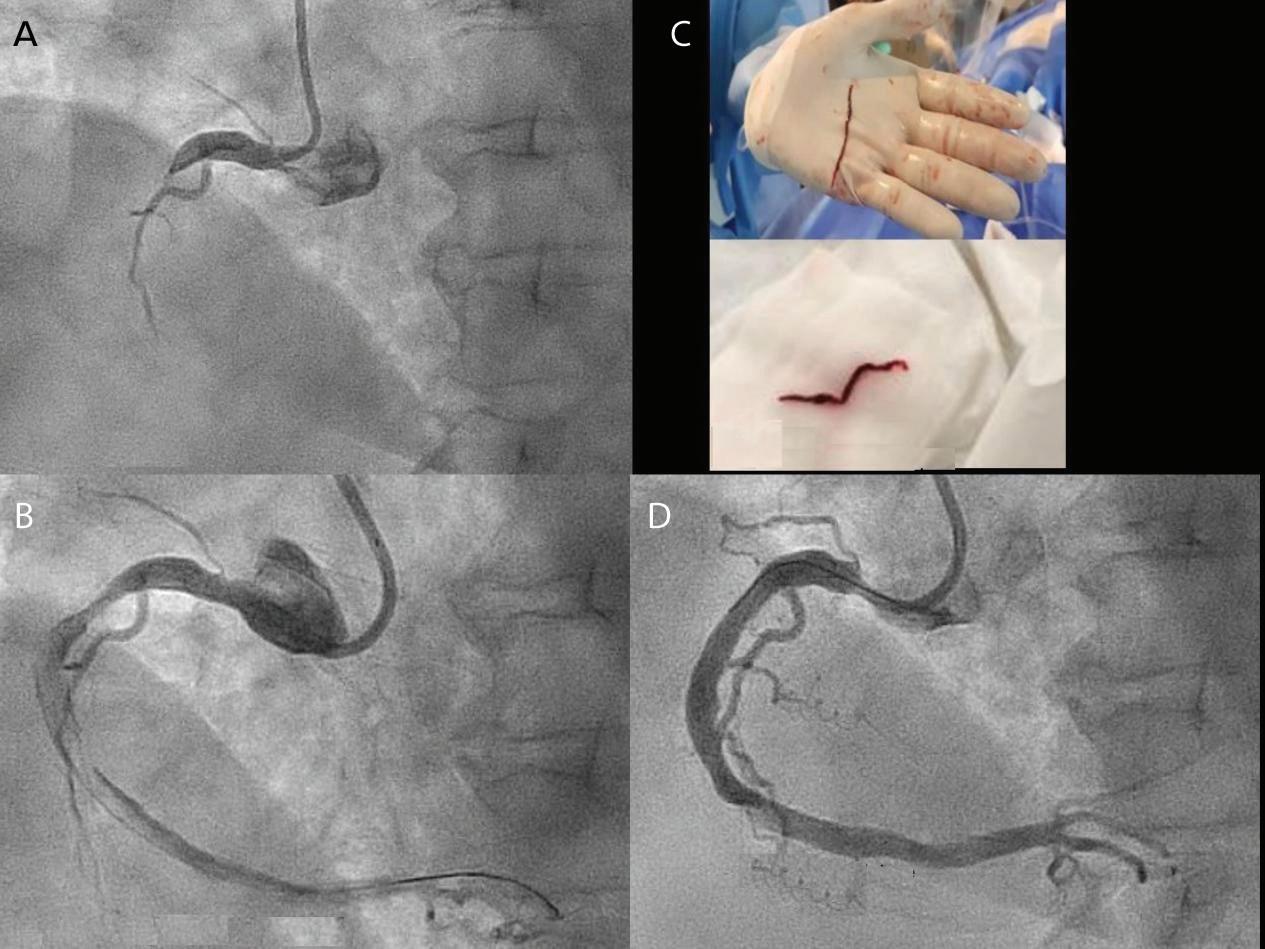

A 57-year-old man presented with a three-decade history of recurrent episodes of palpitation with alarming jugular venous pulsation, but without syncope. Each episode spontaneously reverted to the normal sinus rhythm 6–8 hours after the onset. Cardiac auscultation raised the suspicion of underlying rheumatic mitral stenosis. A 12-lead ECG was suggestive of a WPW pattern with a right posterior septal accessory pathway (Figure 1A). A chest X-ray in the posterior–anterior view was consistent with cardiac auscultation (Figure 1B). A transoesophageal echocardiogram confirmed rheumatic mitral stenosis (Figure 2A and Supplementary Material Video 1). The pliable mitral valve area was 0.8 cm2 and the mean gradient was 17 mmHg at a heart rate of 87 BPM. The coronary angiogram was normal.

The day before the procedure, the patient developed an episode of palpitation during the clinical round. A 12-lead ECG revealed atrial flutter with right bundle branch aberrancy on metoprolol succinate (Figure 2B). The patient’s blood pressure was 124/80 mmHg. Oral verapamil was initiated and the atrial flutter reverted to normal sinus rhythm.

On the day of the procedure, the first balloon mitral valvotomy was performed from a right femoral approach using a 23–26 mm Accura balloon (Vascular Concepts) after transeptal access using an 8 Fr SL-1 sheath and a BRK-0 needle (St Jude Medical). A transeptal puncture was performed after proper needle tip position was confirmed by fluoroscopy (right anterior oblique, left anterior oblique and 90° lateral views) and transoesophageal echocardiography (bicaval and short axis views; Figure 3A). The mean left atrial pressure prior to the valvotomy was 31 mmHg. The balloon was inflated to 26 mm in the right anterior oblique 20° position under fluoroscopy (Figure 3B) because the patient was 160 cm tall. The mitral valve area increased to 2.2 cm2 without any additional mitral regurgitation, and the mean left atrial pressure decreased to 12 mmHg without any mitral valve gradient. Immediate transthoracic echocardiography showed that the mitral valve gradient had decreased to 7/2 mmHg with negligible mitral regurgitation.

Because the patient had baseline pre-excitation through the right posterior septal path and atrial flutter with orthodromic conduction with right bundle branch aberration, one decapolar catheter in the coronary sinus and a quadripolar catheter in the right ventricle were used to study the effective refractory period (ERP) of the accessory pathway rather than using the routine four electrophysiology catheters (three quadripolar [high right atrial, His bundle, right ventricle apex] and one decapolar catheter in the coronary sinus; Figure 4C). The supra-His conduction time was 65 ms and the infra-His conduction time was 9 ms. The baseline ECG was suggestive of a right posterior septal pathway. Right ventricular pacing showed eccentric conduction up to 450 ms, which suggested a retrograde pathway ERP of 450 ms. On pacing the integrated pathway, the ERP was found to be 450 ms. Due to the weak nature of the accessory pathway, ablation was not performed. On rapid atrial pacing, atrial flutter with right bundle branch aberrancy was induced, similar to the clinical tachycardia observed earlier. Ablation for the atrial flutter was not performed, and the patient was maintained on metoprolol succinate and an oral anticoagulant

Figure 1: ECG and Chest X-Ray

Report confirmed by I II IR aVR V1 V2 V3 V4 V5 V5 aVL aVP A B A: A 12-lead ECG showing the Wolff–Parkinson–White pattern with a possible right posterior septal accessory pathway because the R/S ratio is <0.5 in V1 and V2 and <1 in the inferior leads. B: Chest X-ray in the posterior–anterior view showing mitralisation of the left heart border, double atrial shadow on the right

side and a horizontal left bronchus. A: There was significant mitral stenosis and the mean mitral valve gradient of 16 mmHg prior to the balloon mitral valvotomy. B: Atrial flutter with 2:1 atrioventricular block and right bundle branch aberrancy was evident during the electrophysiological study by pacing the atria with a decapolar catheter in the coronary sinus at cycle length of 200 ms.

Figure 4: Electrophysiology Study to Map the Accessory Pathway

Figure 3: Transsepetal Puncture for Balloon Mitral Valvotomy and Electrophysiology Study in One Go A: Septal puncture using fluoroscopy and transesophageal echocardiography guidance. B: A 23–26 mm Accura balloon was inflated to 26 mm in the right anterior oblique view. Electrophysiological study using one quadripolar catheter for right ventricle pacing and one decapolar catheter in the coronary sinus.